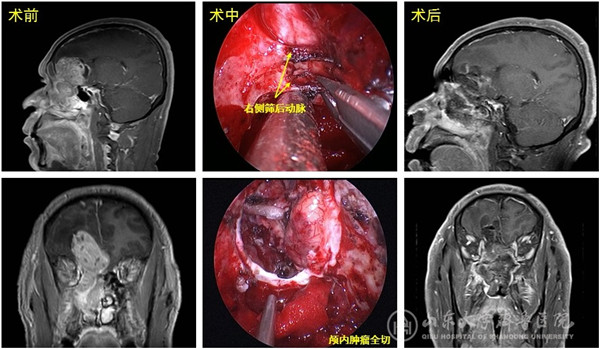

患者48岁,因持续性鼻塞1个半月入院,MR显示右侧鼻颅贯通性肿物,大小约10cmx5cmx4cm,占据右侧额叶、筛窦及整个右侧鼻腔,右侧额窦、蝶窦及上颌窦口受累并堵塞;病变侵犯并突破硬脑膜,周围脑组织及侧脑室受压明显,脑水肿范围大、脑中线结构左移,肿瘤包绕双侧额眶动脉,与大脑前动脉及视神经关系密切。术前活检病理提示嗅神经母细胞瘤。患者入院前已辗转省内及北京多家医院,但因手术难度大、风险高,均未能得到治疗。

入院后李学忠教授组织耳鼻喉科、神经外科、神外重症监护及麻醉科进行了充分讨论,手术由冯昕及倪石磊共同主刀完成,戚其超医师和徐佳宁医师担任助手。术中开放双侧全组鼻窦并彻底切除鼻腔鼻窦的肿瘤,显露并保护双侧眶尖、前颅底、视神经及颈内动脉管,后采用美国匹兹堡大学内镜颅底中心“双人四手”技术操作,电凝双侧筛前、筛后动脉阻断肿瘤供血,仔细分离并完整切除颅内肿瘤及肿瘤起源的嗅球、嗅束,完好地解剖并保护被肿瘤包绕的大脑前动脉重要分支。肿瘤切除后前颅底缺损5cmx5cm,同期取右股外侧阔筋膜及鼻腔带蒂粘膜瓣重建颅底缺损。该肿瘤血运极为丰富,但由于手术策略成功,术中仅出血约500ml;同时手术全程经鼻腔完成,没有颌面部刀口;术中确切的颅底重建阻隔了有菌的鼻腔环境,为患者的快速康复扫清了最后障碍。术后患者转入神外重症监护病房,由黄齐兵主任医师、张源医师、晏骖主治医师共同监护度过了术后恢复期,后转回耳鼻喉科病房,患者各项神经功能保护良好,恢复到正常生活状态,于近日康复出院,患者及家属非常满意手术效果。术后病理为高级别嗅神经母细胞瘤。